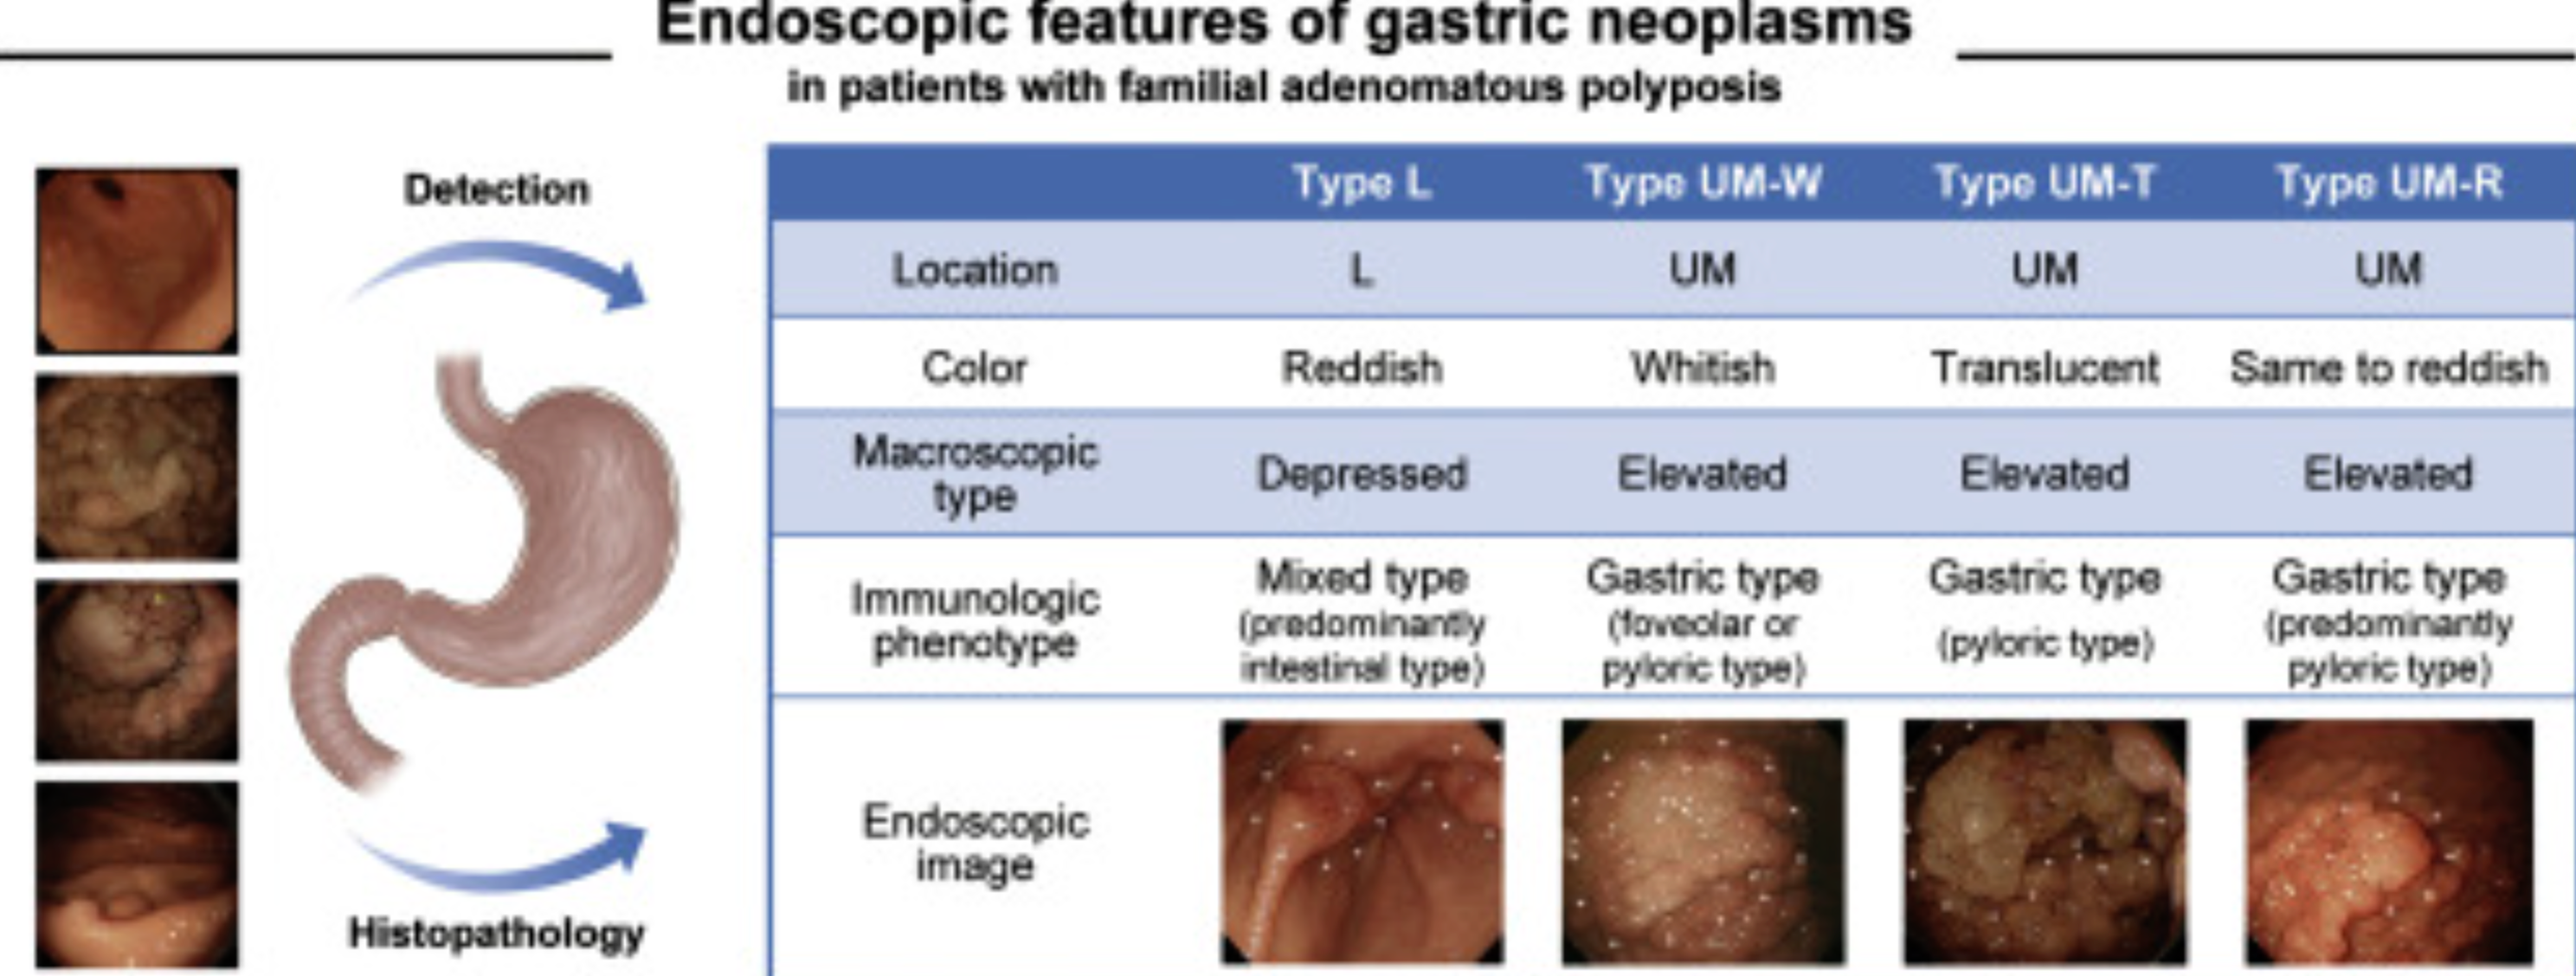

- 53% of patients with familial adenomatous polyposis or Gardner’s syndrome